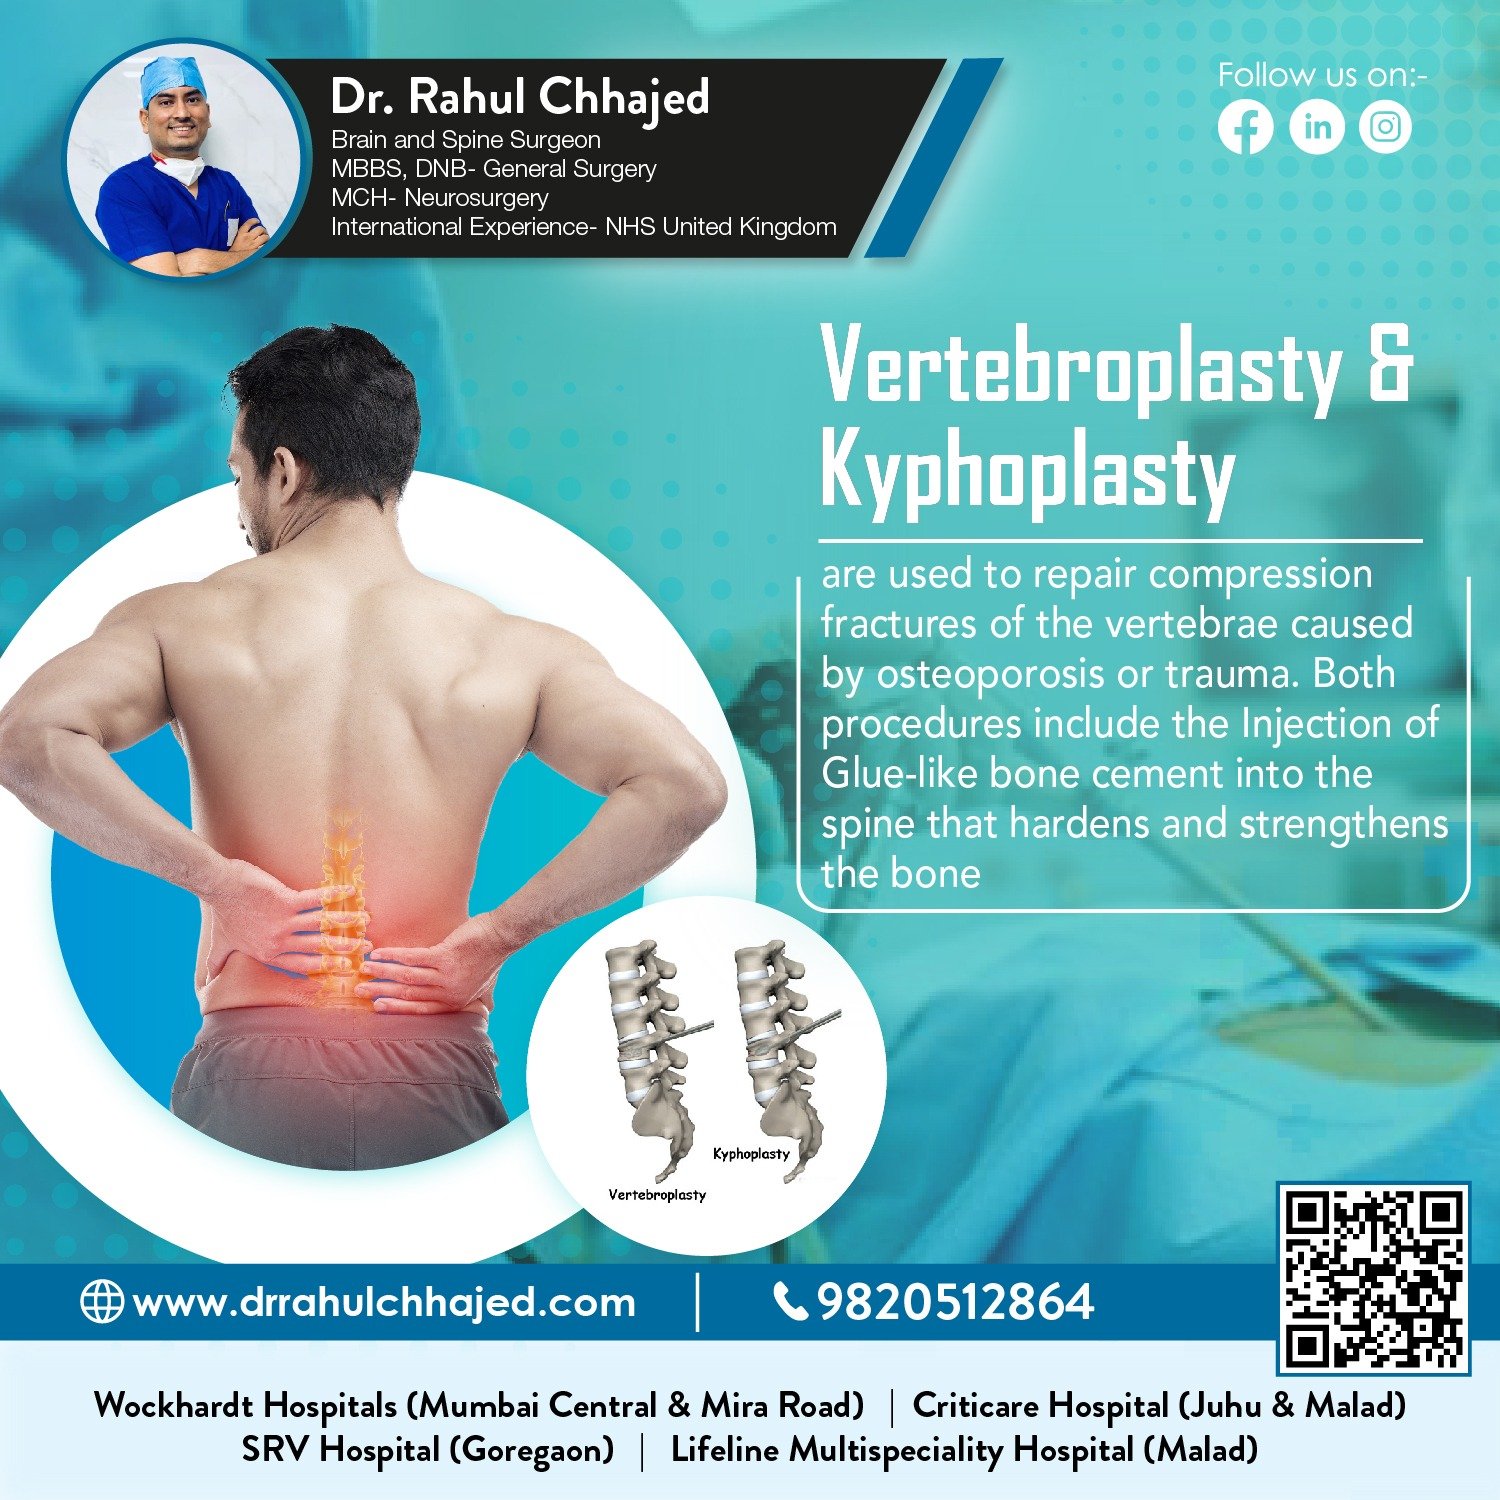

Spine Surgery

Dr. Rahul is a highly experienced spine surgeon specializing in diagnosing and treating spinal conditions. He performs a wide range of surgical options for spinal conditions, including minimally invasive techniques, spinal fusion, and disc replacement.